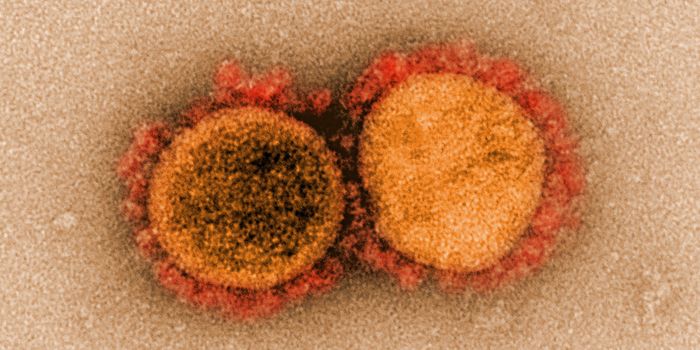

MAR 14, 2022ImmunologyThough it may happen at different rates for different microbes, mutations happen, and SARS-CoV-2, the virus that causes ...

FEB 08, 2022Clinical & Molecular DXViral experts are still unsure where and how the Omicron variant originated, but one thing is clear: it has overt ...

JAN 18, 2022ImmunologyThe Omicron variant was first reported in November 2021. More recently, a surge of infections worldwide has led to wides ...

DEC 06, 2021MicrobiologySino Biological Newly Launched A Panel of Research Reagents for SARS-CoV-2 Omicron Variant (B.1.1.529) Beijing, China, D ...

NOV 26, 2021MicrobiologyOn Thursday, November 2021, South African health officials announced that they had identified a new variant of the pande ...

NOV 11, 2021MicrobiologyWhile many people are most familiar with the coronavirus that causes COVID-19, which is called SARS-CoV-2, there are man ...

NOV 01, 2021Cell & Molecular BiologyResearchers have learned a lot about the SARS-CoV-2 virus since the start of the COVID-19 pandemic. We know that he viru ...

SEP 07, 2021MicrobiologyThe world has rapidly become familiar with sarbecoviruses, two of which jumped to humans in recent years. The first was ...

MAY 10, 2021MicrobiologyThe pandemic virus SARS-CoV-2 has changed the world in devastating ways, taking hundreds of thousands of lives & new var ...

JAN 24, 2021MicrobiologyTo cause the COVID-19 illness, the SARS-CoV-2 virus first has to get into cells. To do so, it uses something called a sp ...

JAN 23, 2021MicrobiologyAbout a year ago, I wrote about the virus that would come to be known as SARS-CoV-2 for the first time. And while we've ...